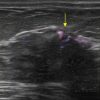

Ung thư vú

» Thông tin: Nữ giới – 76 tuổi.

» Lâm sàng: Khối tuyến vú.